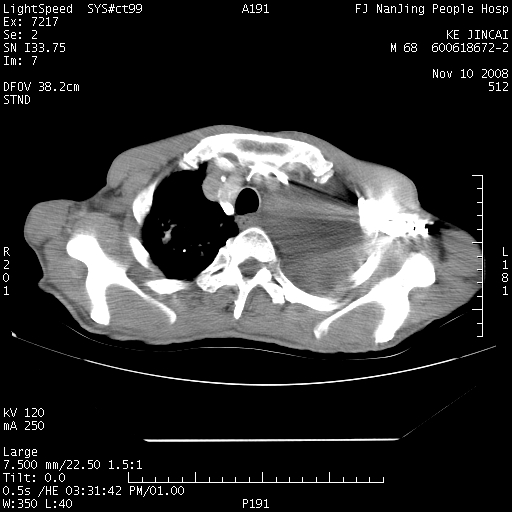

是个很有看头的病例,咋人气那么不旺?没多少人兴趣呢?这个病例几大怪:1   恶性肿瘤侵犯心肌左房怪,心肌一般不会被恶性肿瘤侵犯吧?2   左下肺均匀实变怪,内无含气,有别一般不张实变,含气肺泡完全为液体取代,而非一般不张实变的肺萎陷,冷不丁还以为是肿大的脾脏3   肿瘤本身怪,像tb肺不张4   这么有看头的病例没人气怪。呵呵。

左肺恶性肿瘤侵犯肺动脉,左心房内瘤栓,胸膜转移。

左肺恶性肿瘤侵犯肺动脉,左心房内瘤栓,胸膜转移,少见,学习了。